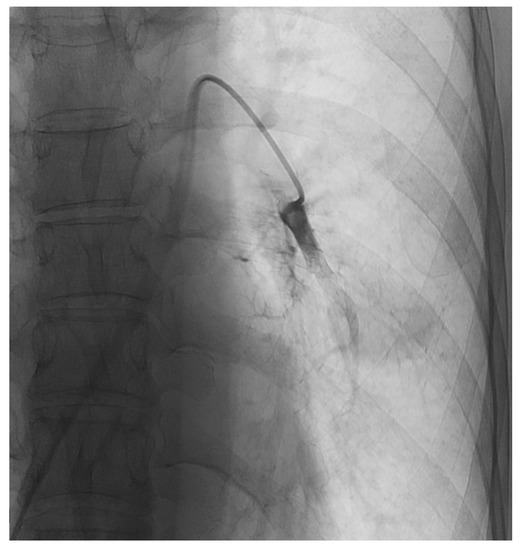

2.6. TPCE Procedure